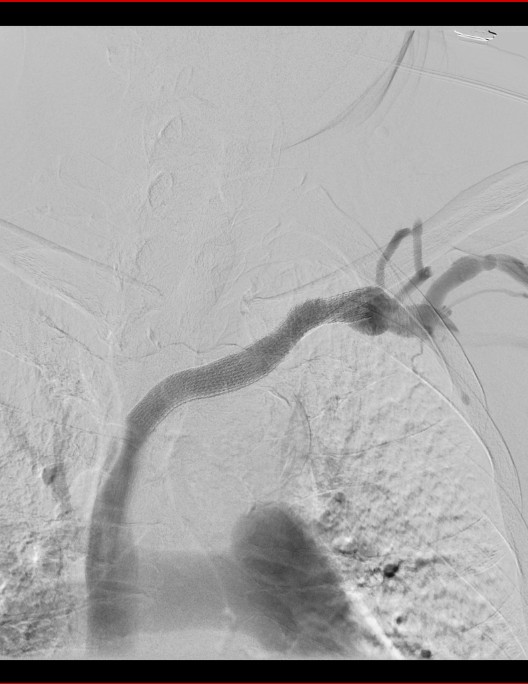

DAS检查发现应该存在的血管回流通路闭塞了。

经过DSA下PTA扩张及安放VIABAHN覆膜支架,消失的血管重新出现。

术前

术后